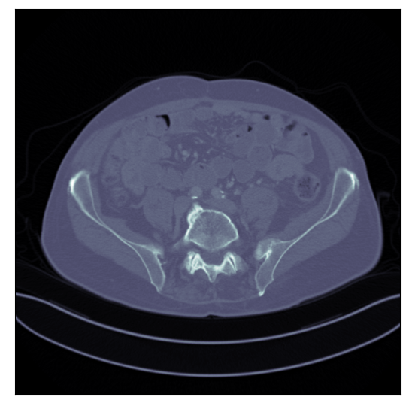

We consider the variational reconstruction framework for inverse problems and propose to learn a data-adaptive input-convex neural network (ICNN) as the regularization functional. The ICNN-based convex regularizer is trained adversarially to discern ground-truth images from unregularized reconstructions. Convexity of the regularizer is desirable since (i) one can establish analytical convergence guarantees for the corresponding variational reconstruction problem and (ii) devise efficient and provable algorithms for reconstruction. In particular, we show that the optimal solution to the variational problem converges to the ground-truth if the penalty parameter decays sub-linearly with respect to the norm of the noise. Further, we prove the existence of a sub-gradient-based algorithm that leads to a monotonically decreasing error in the parameter space with iterations. To demonstrate the performance of our approach for solving inverse problems, we consider the tasks of deblurring natural images and reconstructing images in computed tomography (CT), and show that the proposed convex regularizer is at least competitive with and sometimes superior to state-of-the-art data-driven techniques for inverse problems.